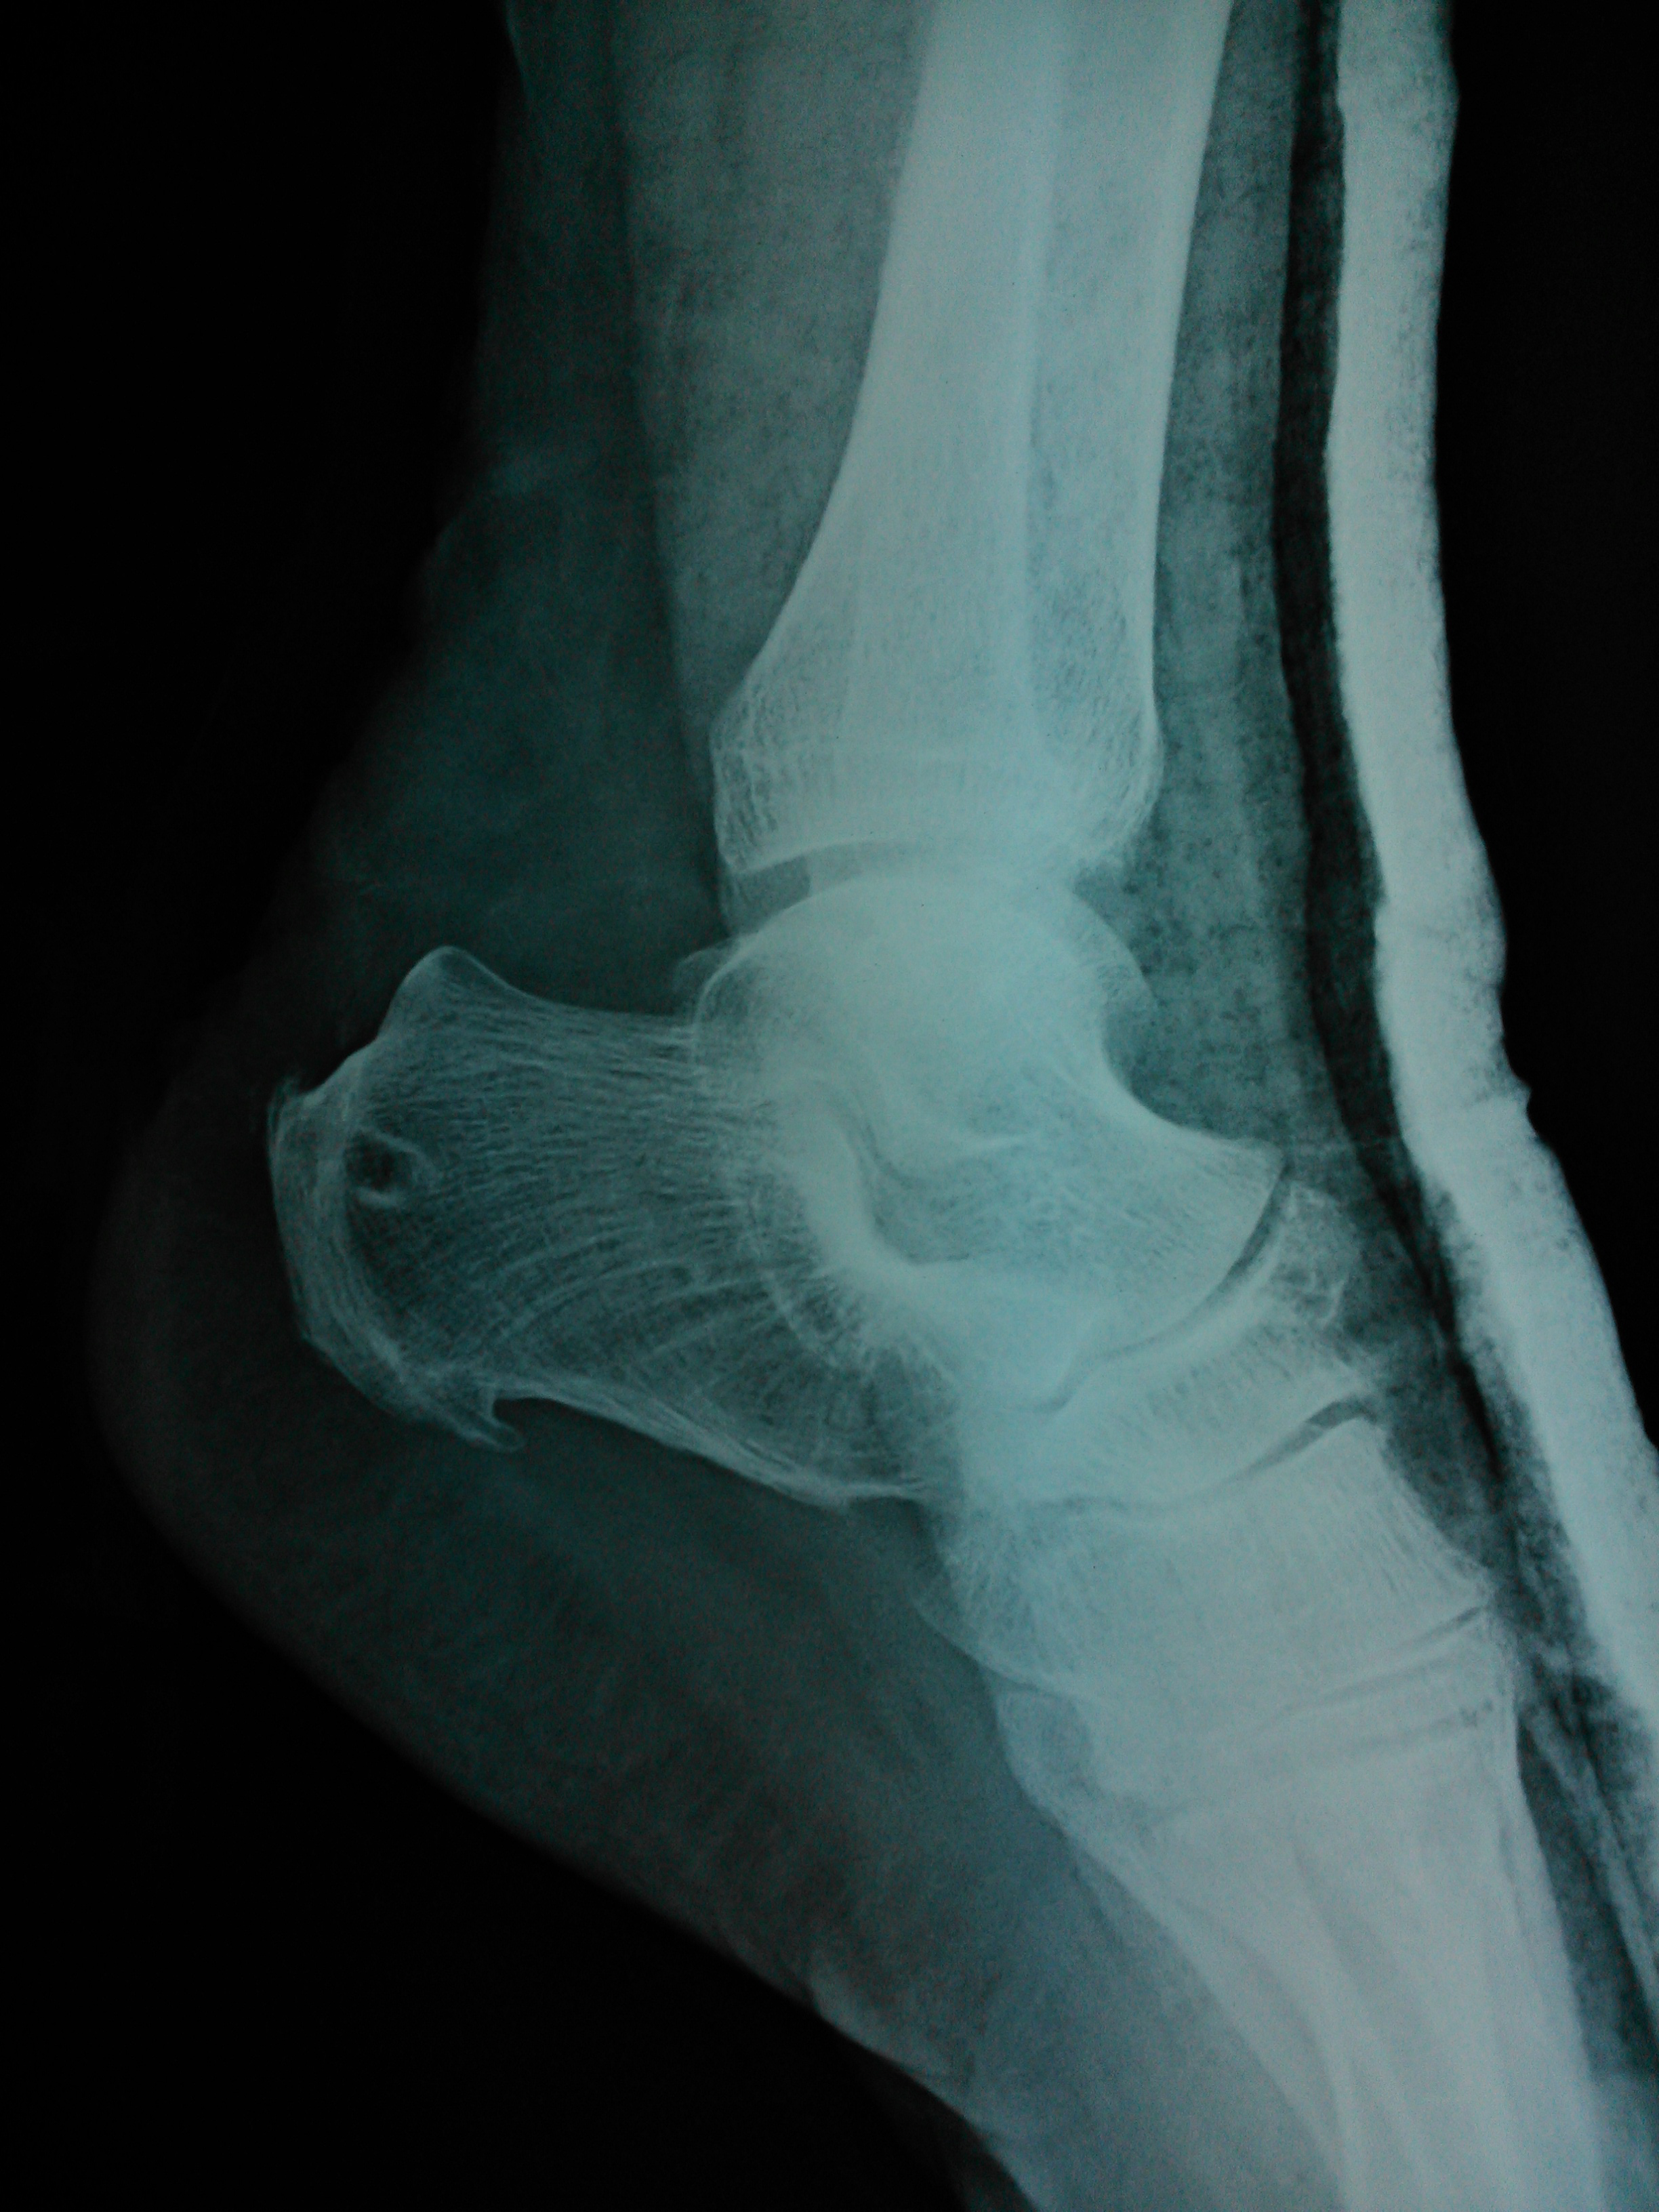

Prophylactic antibiotics are administered, anaesthesia is attained, a tourniquet is applied to the proximal thigh and the patient is positioned prone on the operating table. The whole leg is prepped and draped distal to the tourniquet, which is inflated after limb exsanguination with a sterile esmach bandage. A traditional paramedian incision, approximately 15 cm long, medial to the Achilles tendon is performed to avoid injury to the sural nerve. The incision is deepened directly down to the paratenon, which is incised longitudinally to expose the ruptured tendon and bone. We avoid making the flaps superficial to the paratenon so as not to undermining the blood supply to the skin. The distal part of the incision is over the calcaneal tuberosity and full thickness flaps are raised in both directions to the sides of the bone. Once the distal nature of the rupture is verified (Figure 1) the retrieval of the ipsilateral semitendinosus tendon graft is commenced. For the harvest the posterior mini-incision hamstring graft technique described by Prodromos et al. is utilized.4 A small, 3 cm long, incision is made over the semitendinosus on the medial border of the popliteal fossa, the tendon is easily identified and delivered out of the incision (Figure 2a). An index finger follows the tendon proximally and distally. An open striper is first used to free the proximal part of the tendon. Then any fibrous attachments to the tendon, as well as the accessory semitendinosus are easily identified and cut. Finally, with the knee flexed, the index finger follows the tendon to its insertion and where the skin is tented anteriorly a second small, 2 cm, incision is made. The tendon is delivered through the second incision and finally is cut (Figure 2b). The two ends of the tendon graft are prepared by removing any muscle and sutured with No. 2 polyester in an alternating interlocking fashion for 2-3 cm, with at list 5 perforation on each side. The tendon is then subjected to forceful and cyclic loading, its diameter is measured and finally it is stored in moist gauze. The appropriate drill is selected, usually 4.5 mm, and with the help of a drill sleeve, a hole is made just distal to the insertion of the Achilles tendon in the calcaneal tuberosity (Figure 3). With a suture passer one end of the tendon and one or two No. 5 polyester sutures are passed through the drill hole (Figure 4). The tendon stump is cleaned from any degenerated tissue and temporarily approximated to its insertion point with a simple running suture without significantly reducing its length. The two ends of the tendon graft are weaved to each side of the Achilles tendon using a Pulvertaft-like technique (Figure 5). Finally the two sutures ends are tied together. The No. 5 suture is used to suture the Achilles tendon and the graft together, using a Krackow technique, over the whole length of the graft, along each side of the tendon and the two ends are tied proximally (Figure 6). Finally a second No. 5 suture may be used in a modified Kessler technique. The sutures are initially passed through the distal stump. A No. 10 drain is inserted deep to the tendon. The paratenon is then sutured, followed by the subcutaneous tissue and finally the skin. An anterior splint is used to immobilize the ankle in 20-25 degrees of plantarflexion (Figure 3).

Figure 3 Position of the tunnel on the calcaneus on a lateral radiograph.